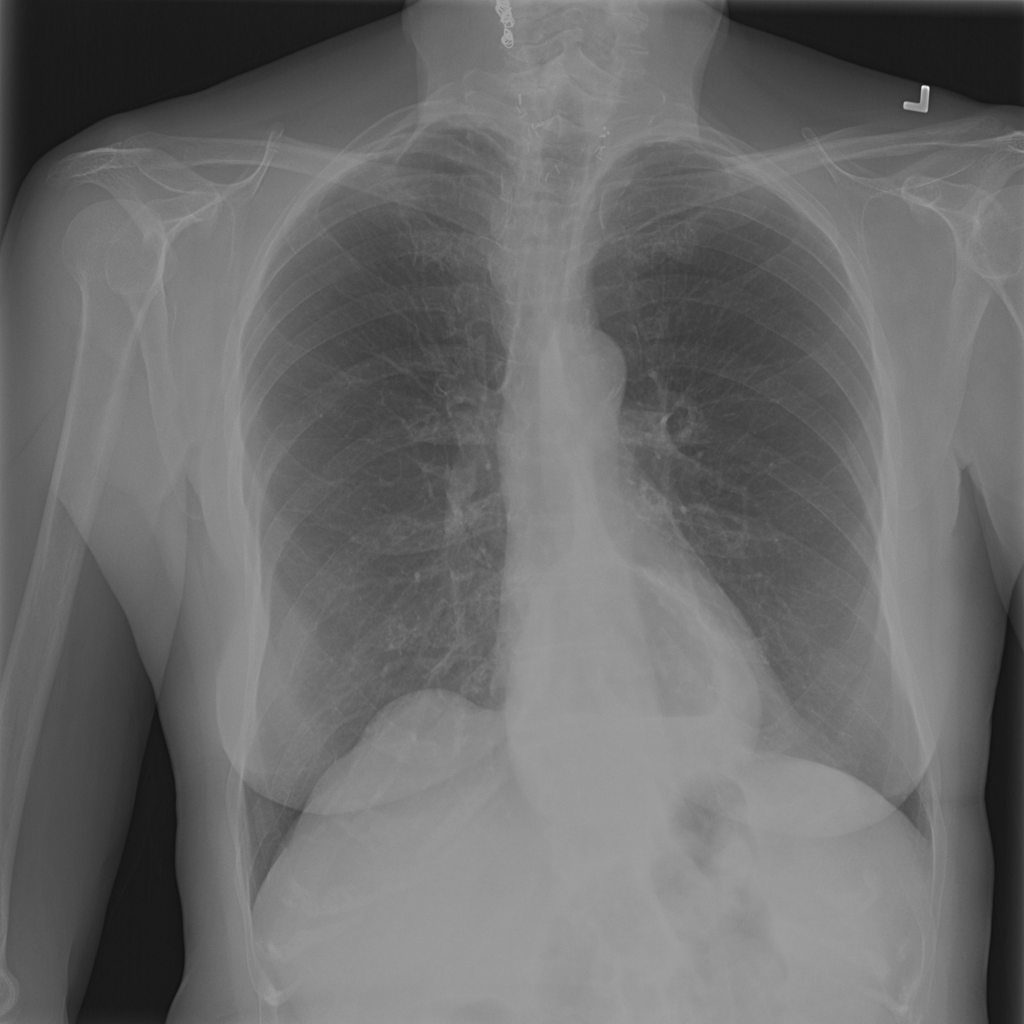

PAT-C048 · IMG-001Hernia

PAT-C048 · IMG-001

PA